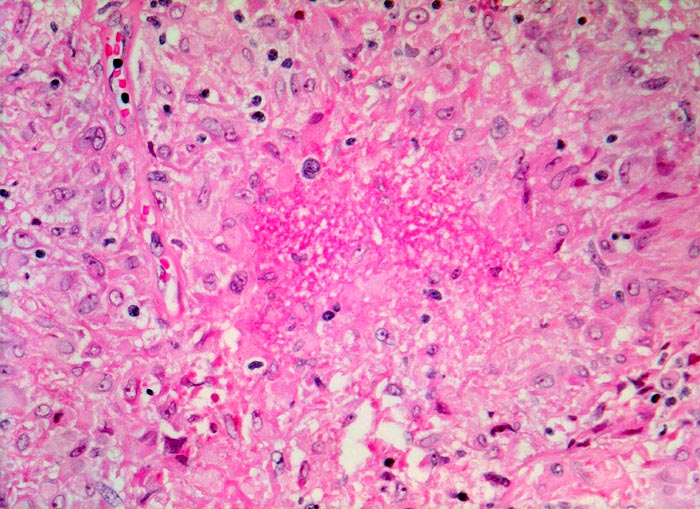

Sarkoidosegranulome bestehen aus Epitheloidzellen mit einem peripheren Lymphozytensaum. Mehrkernige Riesenzellen, meistens solche vom Langhans-Typ mit hufeisenförmig angeordneten Kernen und Asteroidkörperchen (> 4173) können zusätzlich vorhanden sein. Diese Granulome enthalten meist keine Nekroseherde (=produktives Granulom). Man findet diesen Granulomtyp hauptsächlich in Lymphknoten, aber auch in inneren Organen und in der Haut. Die Sarkoidosegranulome zeigen in späteren Stadien eine charakteristische perigranulomatöse und die Granulome septierend unterteilende Fibrose (> 4015).

• Konfluierende Granulome aus grossleibigen Epitheloidzellen.

• Wenige mehrkernige Riesenzellen.

• Kleinere Nekroseareale im Zentrum grösserer Granulome. (Die Nekrosen sind untypisch für die Sarkoidose, können aber bei grossen Granulomen gelegentlich vorkommen).